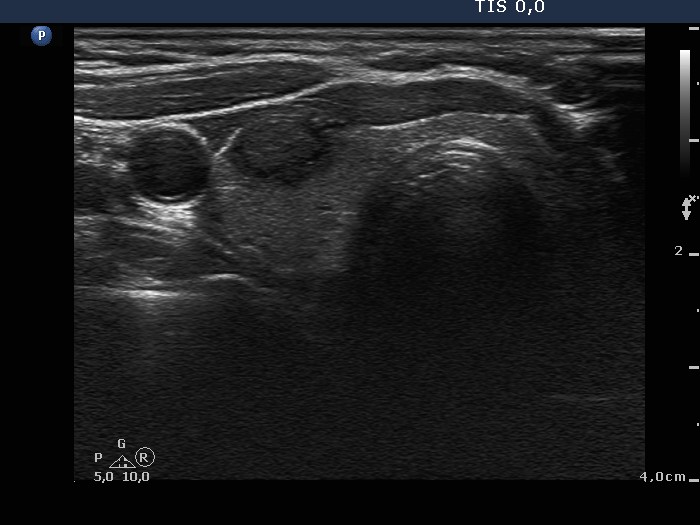

Clinical presentation: A 68-year-old woman was referred for an evaluation of a nodule discovered on ultrasonography. She was treated for breast cancer which gave metastasis to the lung.

Ultrasonography: There was a hypoechogenic nodule with cotton-like hyperechogenic patches and smaller punctate hyperechogenic granules in the right lobe. The nodule presented a type 3 vascular pattern, i.e. intranodular blood flow.